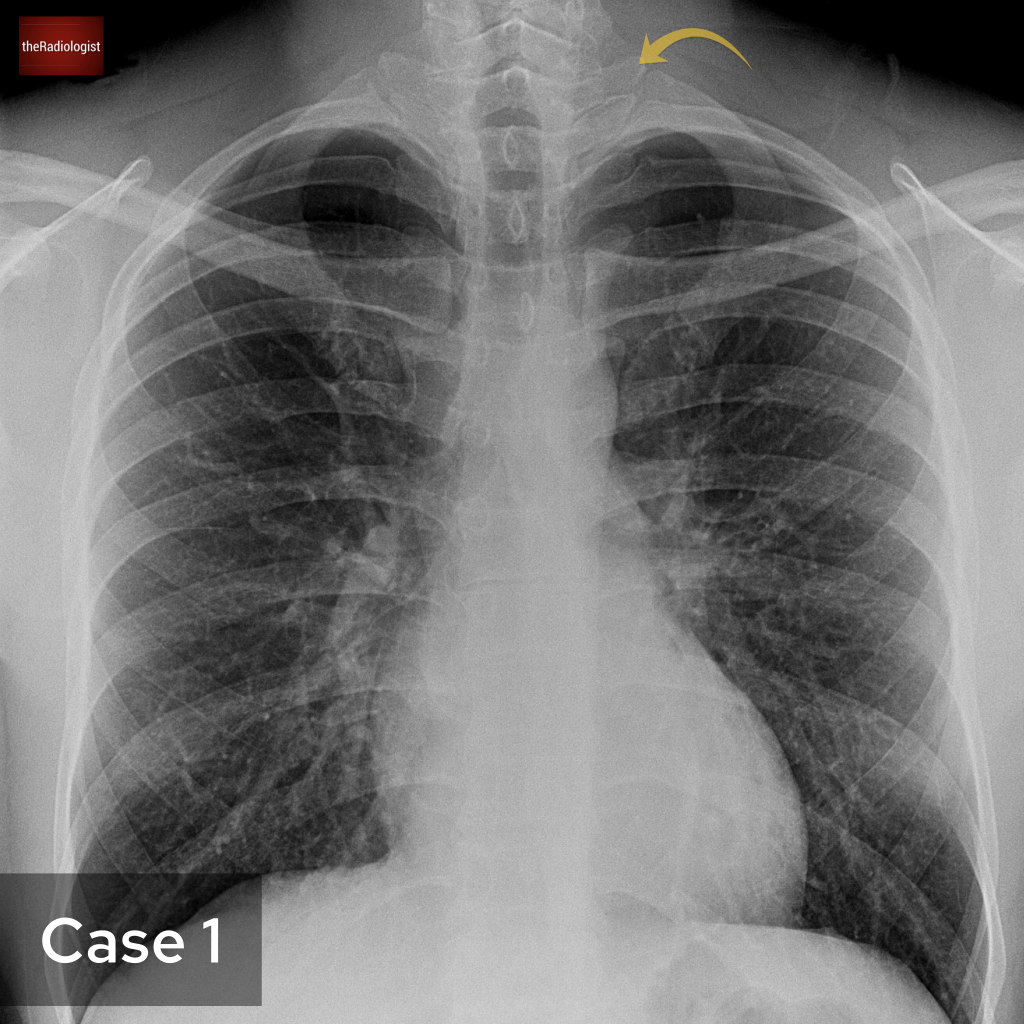

Case 1

Let’s start with a PA chest X-Ray. What is the arrow pointing at?

Choose one from the following options: